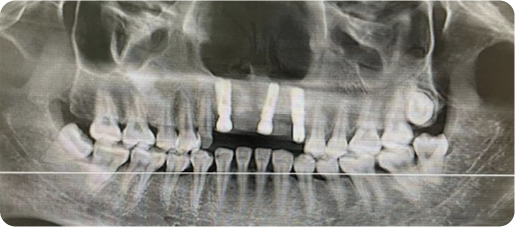

Half Arch Dental Implant Case

BEFORE

VS

AFTER

Name:Mrs zhangAge:40

Evaluation: The patient presents with compromised masticatory function and severealveolar bone resorption secondary to long-term use of a removable denture

Treatment Plan:The patient underwent bilateral maxillary sinus augmentation to restore masticatory function in the upper arch, and three implants were placed in the mandible, supporting a 4-unit prosthesis to restore masticatory function.

Patient Feedback:It feels just like my own teeth— I can eat anything I want with confidence, and they're so comfortable and natural-looking that I forget they're not real.For Prevention:Maintain meticulous oral hygiene and adhere to a schedule of regular professional maintenance; these measures are essential for achieving optimal functional longevity of your dentition.